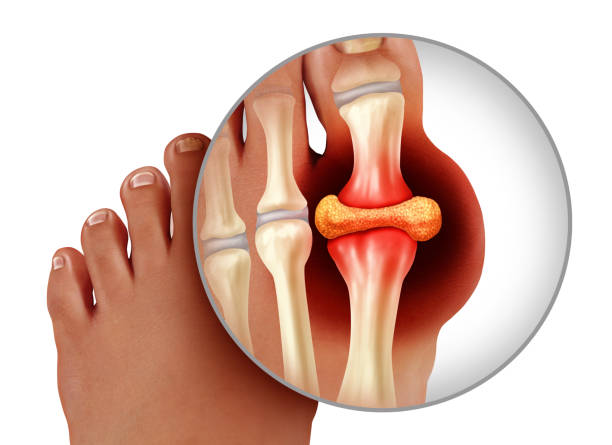

통풍은 요산이 체내에 가득하게 쌓이면서 생기는 질환입니다. 요산은 우리가 먹은 음식이 소화되고 최종적으로 남은 물질로 혈액 내 녹아 소변으로 배출되는데 요산이 과도하게 쌓이면 결정체로 변하게 되고 이 결정체가 관절 내에 침착하여 염증을 유발하게 되기 때문에 이번 시간에는 통풍 증상과 통풍 치료법에 대해 알아보도록 하겠습니다.

통풍 증상 두 번째는 엄지발가락 통증입니다. 처음에 주로 엄지발가락 근저부 관절에 발병하는데 돌발적인 통증과 함께 붉게 부어오르며 무릎, 손목, 발목, 팔꿈치 등에 발생하기도 합니다.